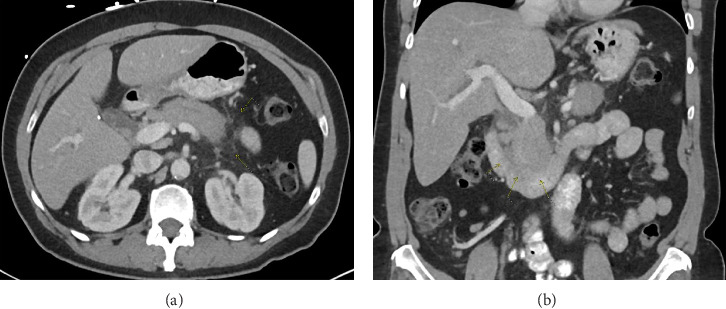

Introduction: Autoimmune pancreatitis (AIP) and pancreatic cancer are top differentials of obstructive jaundice originating from the pancreas. Case Description/Methods: The patient's findings were concerning for malignant biliary obstruction, but a thorough workup determined that the patient had AIP-NOS. She underwent EBS and was discharged on a steroid taper. Follow-up demonstrated complete resolution of symptoms, laboratory markers, and imaging. Conclusion: Adequate pancreatic tissue is not always obtained with 22-gauge needles. Biliary stenting is justifiable in AIP with significant hyperbilirubinemia. It is important to consider AIP for with a pancreatic head mass and obstructive jaundice to optimize outcome.

Abstract Image